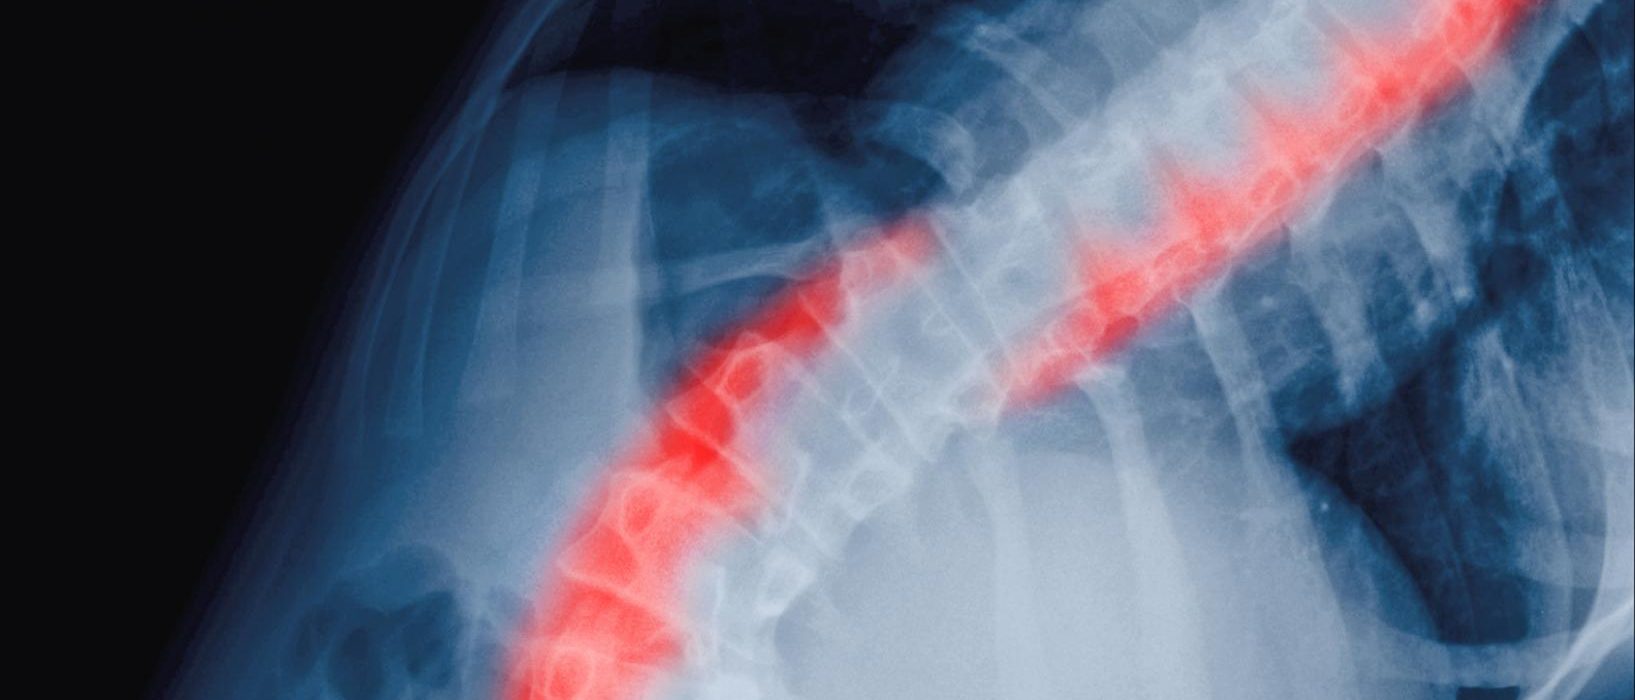

Skoliose: Manuellterapi er potensielt effektivt

2-3 prosent av barn og unge i alderen 10-16-år har idiopatisk skoliose (skjev rygg uten kjent årsak). Konservativ behandling i form av øvelser hos fysioterapeut har vært omdiskutert. I en oversiktsartikkel har forskere sett på om manuellterapi som tillegg til øvrig konservativ behandling, kan være effektivt.

14 artikler, både casestudier, observasjonsstuder og RCT, ble funnet og inkludert i forskningsmaterialet. Casestudiene og de mindre studiene som inngår i oversikten, gjør at det ikke kan trekkes noen klare konklusjoner. Forfatterne skriver likevel at funnene gir grunnlag for å anta at manuelle teknikker som myofascial release og spinal manipulasjon potensielt er effektive som tillegg til annen konservativ behandling. Flere høykvalitets-studier er imidlertid nødvendig for å kunne treffe sikre konklusjoner.